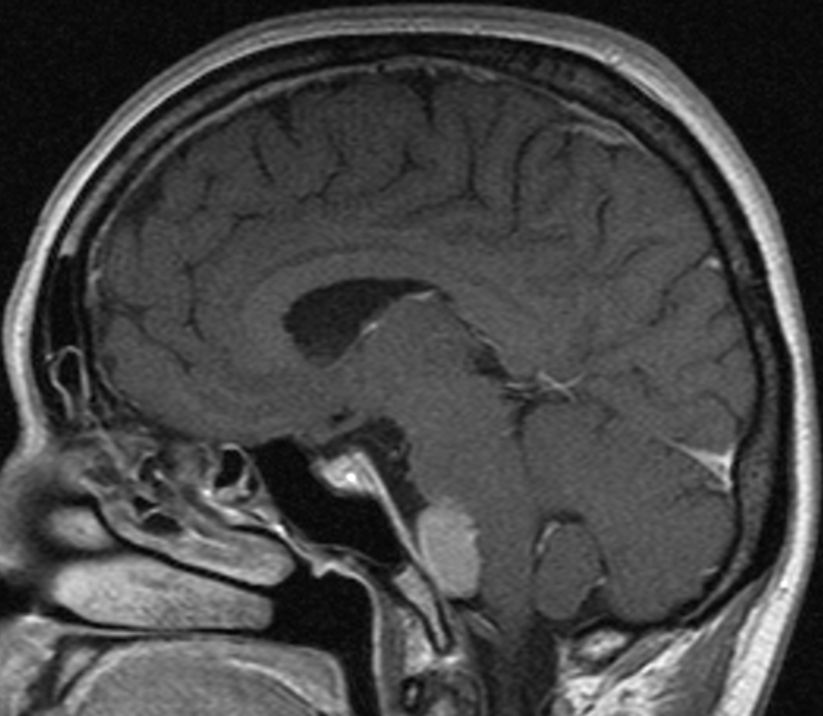

| MRT eines Meningeoms des Tentoriums |

| 72-jährige Patientin mit Teilparese des rechten Beins, passageren Sprachstörungen und Krampfanfall vor 6 Monaten. Postoperative Histologie: Meningeom Grad 1 | CT vor KM-Gabe . |